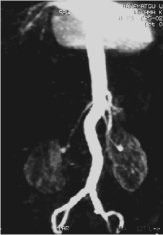

TOF: 3D FGRE/FSPGR scan

3D FastTOF is a FastGRE or SPGR sequence designed for use in vascular imaging. 3D Fast TOF provides the benefits of a 3D acquisition with the use of faster TRs and TEs to decrease imaging time.

Use Fast 3D TOF-GRE and Fast TOF-SPGR (CEMRA [Contrast Enhanced Magnetic Resonance Angiography]) with SmartPrep or Fluoro Trigger to acquire signal change over time to evaluate vascular disease.